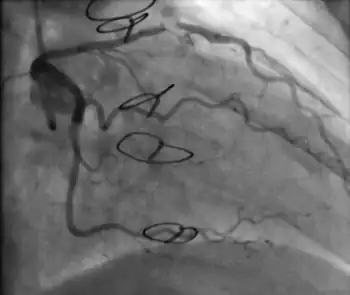

Coronary angiography

Surveillance is performed by regularly repeating coronary angiography in the cardiac catheterization laboratory, the diagnostic test of choice.[2] This is typically performed annually for the first five years after transplantation.[8] Angiography in CAV characteristically demonstrates diffuse stenoses in large coronary arteries and a reduced number of smaller coronary arteries, also known as "peripheral pruning".[2][6] However, because CAV frequently affects the entire length of the coronary artery, CAV may not be apparent by angiography alone.[2]

Occlusion of the right coronary artery 2 years after heart transplantation. -